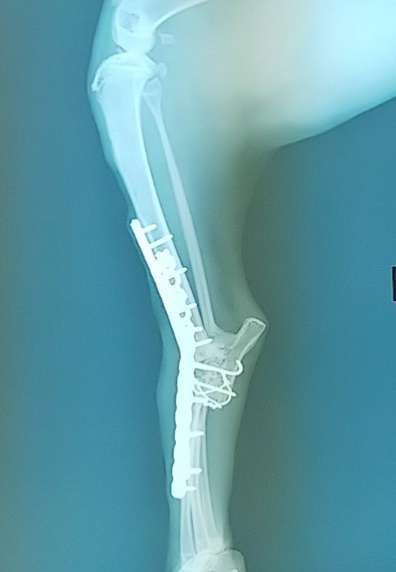

6月26日手術

実は包帯が取れ、やっとしっかり脚を見ることが出来た時、

あまりにも足首が真っ直ぐだったことを疑問に思いました。

返って邪魔になっているのでは?これでは手術した意味がないのでは?

と、とても気になったため担当した大学病院の教授にも確認をしたのですが

分かり難いが角度はあり、あまり角度を付けるのは、入れているプレートの強度の心配もあるから、とのことでした。

そう聞いても、くろまるくんはあまり脚を使わず不便そうに見えていたので

不安に思っていたのですが、最初は違和感があったようで、時間が経った今はちゃんと使えるようになりこれで良かった!と思えるようになりました。